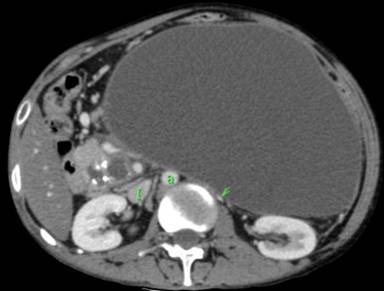

A chronic alcoholic 29-year-old male presented with complaints of heaviness in the scrotum since a few days and lumpish feel in the abdomen since a few weeks. Sonography scrotum revealed multiple dilated, tortuous serpiginous anechoic channels situated on the posterolateral aspect of the left testis (Image 1).These channels were venous in nature and had continuous reversal of flow on Valsalva maneuver. The right testis was normal. On abdominal sonography, there was a 20x12x18 cm huge cystic lesion present predominantly in the epigastrium and left hypochondrium. A CT was performed which confirmed the findings. Besides, there was dilation of the pancreatic duct with calcification in the pancreatic head. The cystic lesion was a huge pseudocyst in the setting of chronic calcific pancreatitis. The pseudocyst was seen to compress the left renal and testicular veins with consequent secondary varicocele on left. There was rightward displacement of the aorta (Image 2: a) and inferior vena cava (Image 2: I). CT in venous phase with coronal reconstruction depicts the huge pseudocyst centered predominantly in epigastrium and left hypochondrium. There is prominence of testicular venous plexus on left (Videoclip). The serum lipase and amylase levels were 501 U/L (reference range: 40-290 U/L) and 1,024 IU/L (reference range: 25-125 IU/L), respectively. A cystogastrostomy was performed which lead to decompression of both the pseudocyst and the varicocele.

Image 2 |